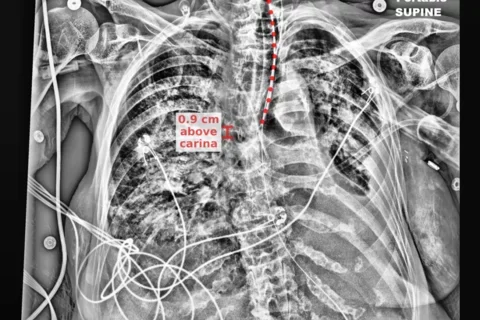

CVIB software engineers KP Wong and Liza Shrestha achieved the landmark of the first image pushed to PACS by any research or commercial AI software at UCLA. Liza led deep learning efforts to automatically detect endotracheal and nasogastric tubes along with the relevant anatomic landmarks to check their position. KP Wong collaborated with UCLA Health IT, OHIA and ISS, to integrate the software into the clinical workflow. Chest x-rays are automatically routed to an AI server for processing and the resulting image pushed back to PACS within minutes where it is available for ICU physicians to perform an initial check of the tube position. The image is also available for ACI radiologists to support their review and reporting. Significant technical collaborations were required to move this technology from the lab successfully into the clinical workflow at UCLA where it can be most impactful on patient care. A quality improvement project is underway to evaluate the usefulness of this investigational software in clinical practice. Within the UCLA environment the AI is running on Microsoft’s Azure cloud and CVIB computer scientist, Matthew Brown, was interviewed by Microsoft about the collaboration.